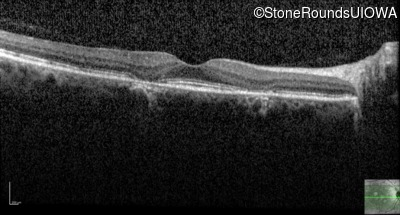

Optical Coherence Tomography - Right - 20/25 +2

Exemplar / OCT Stack

OCT Stack